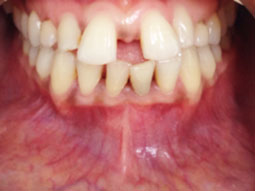

L’anamnèse rapporte un antécédent de traumatisme maxillo-facial ancien, sans prise en charge spécifique, ni suivi stomatologique. L’examen clinique ne montre aucune manifestation inflammatoire au niveau de la muqueuse en regard. La palpation permet de ressentir une dépression élastique au niveau de la zone médiane mandibulaire, en regard de la région apicale des incisives inférieures.

Il révèle également une absence de réponse au test de vitalité pulpaire sur les dents du secteur incisif et au niveau de la canine inférieure gauche, ainsi qu’une légère mobilité, non perçue par la patiente avant la consultation, pour le bloc incisif.

L’examen radiographique montre effectivement une radioclarté apicale au secteur incisivo canin mandibulaire, à contours nets, sans résorption radiculaire associée. Le cone beam réalisé précise le volume exact de la lésion, ses rapports aux apex voisins, et met en évidence la rupture de la continuité de la table externe, liée au volume lésionnel. La table linguale est par endroit érodée, mais continue (2).